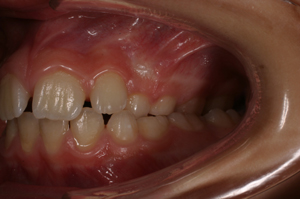

.... Spontaneo riposizionamento dei molari permanenti! Dopo 8 mesi viene tolto il REP! Contenzione con dispositivo elastodontico che guida in eruzione i denti permanenti! Durata: 24 Mesi Inizio Aprile 2006 - Fine Aprile 2008 A fine terapia si cerchera' di evitare un trattamento ortodontico fisso, se cio' sará possibile, finalizzando il caso con un positioner individualizzato!